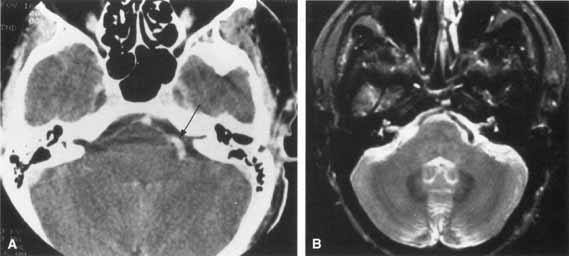

Facial palsies often are produced by closed-head trauma, especially when lateral skull compression has occurred. The resulting temporal bone fractures may be longitudinal or transverse to the axis of the petrous bone (Fig. 14). Longitudinal fractures are more common and usually spare the facial nerve, but if the facial nerve is impaired, the longitudinal fracture usually involves the segment just distal to the geniculate ganglion.82 Paralysis typically results from compression and ischemia rather than direct injury.83 Transverse fractures are associated with facial palsy in about 50% of cases; the facial nerve is usually impaired in the labyrinthine segment proximal to the geniculate ganglion. In transverse fractures, the paralysis is typically more severe and immediate.83

Fig. 14 Skull base showing transverse and longitudinal axes (arrows) of petrous fractures. (Gray H: Anatomy of the Human Body. 26th ed. Philadelphia, Lea & Febiger, 1955)

In a series of 90 cases of temporal bone fractures reported by Cannon and Jahrsdoerfer,83 ecchymosis over the mastoid (Battle's sign) was present in 8 patients. This sign is usually seen when the skull base is fractured and results from blood extravasated along the course of the posterior auricular artery. In longitudinal fractures, rupture of the tympanic membrane is common with associated CSF otorrhea and hemotympanum. Transverse fractures can also cause hemotympanum but are rarely associated with rupture of the tympanic membrane and bleeding from the external canal. The facial nerve is also subject to trauma as it exits the stylomastoid foramen, where it may be impaired by blunt force, knife wounds, or local infiltration of an anesthetic.

Surgical exploration and possible repair in acute traumatic paralysis are indicated in selected cases when the nerve has been crushed, stretched, or transected. Such an injury is likely in cases of temporal bone fracture that have a sudden and complete onset of paralysis, that have displacement of the temporal bone fragments noted by computed tomography (CT) scan, and that have lost the electrical response to stimulation by the fifth day. Surgical exploration in such cases should be undertaken as the patient's condition permits. If an injury occurs accidentally during surgery, repair should be performed at that time.

A history of cancer (particularly involving the breast, lung, thyroid, kidney, ovary, or prostate) associated with a rapidly progressive facial paralysis strongly suggests a metastatic lesion. The facial nerve may be involved by a bony metastasis or by meningeal infiltration. Neuroimaging studies are indicated to search for the primary site and to localize the site of facial nerve involvement (Fig. 17). If these are unrevealing, serial lumbar punctures may be necessary to exclude meningeal carcinomatosis. In some cases, surgical exploration of the temporal bone or of the extracranial course of the facial nerve is recommended to locate the lesion. In one study of meningeal carcinomatosis, the seventh nerve was affected in 15 of 90 patients.95 Facial nerve involvement is often unilateral, but it occurs bilaterally in about 10% of such patients.96

Fig. 17 Axial MRI scan discloses idolinium enhancement and enlargement of right facial nerve (arrow) in patient with meningeal carcinomatosis.